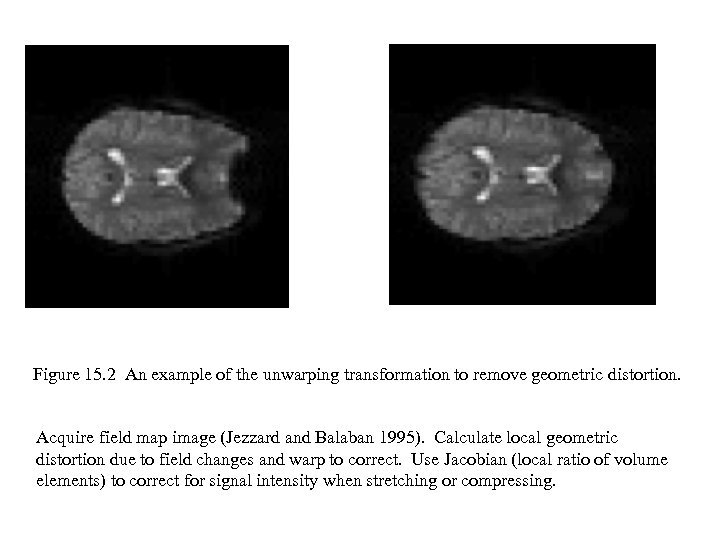

Figure 15. 2 An example of the unwarping transformation to remove geometric distortion. Acquire field map image (Jezzard and Balaban 1995). Calculate local geometric distortion due to field changes and warp to correct. Use Jacobian (local ratio of volume elements) to correct for signal intensity when stretching or compressing.